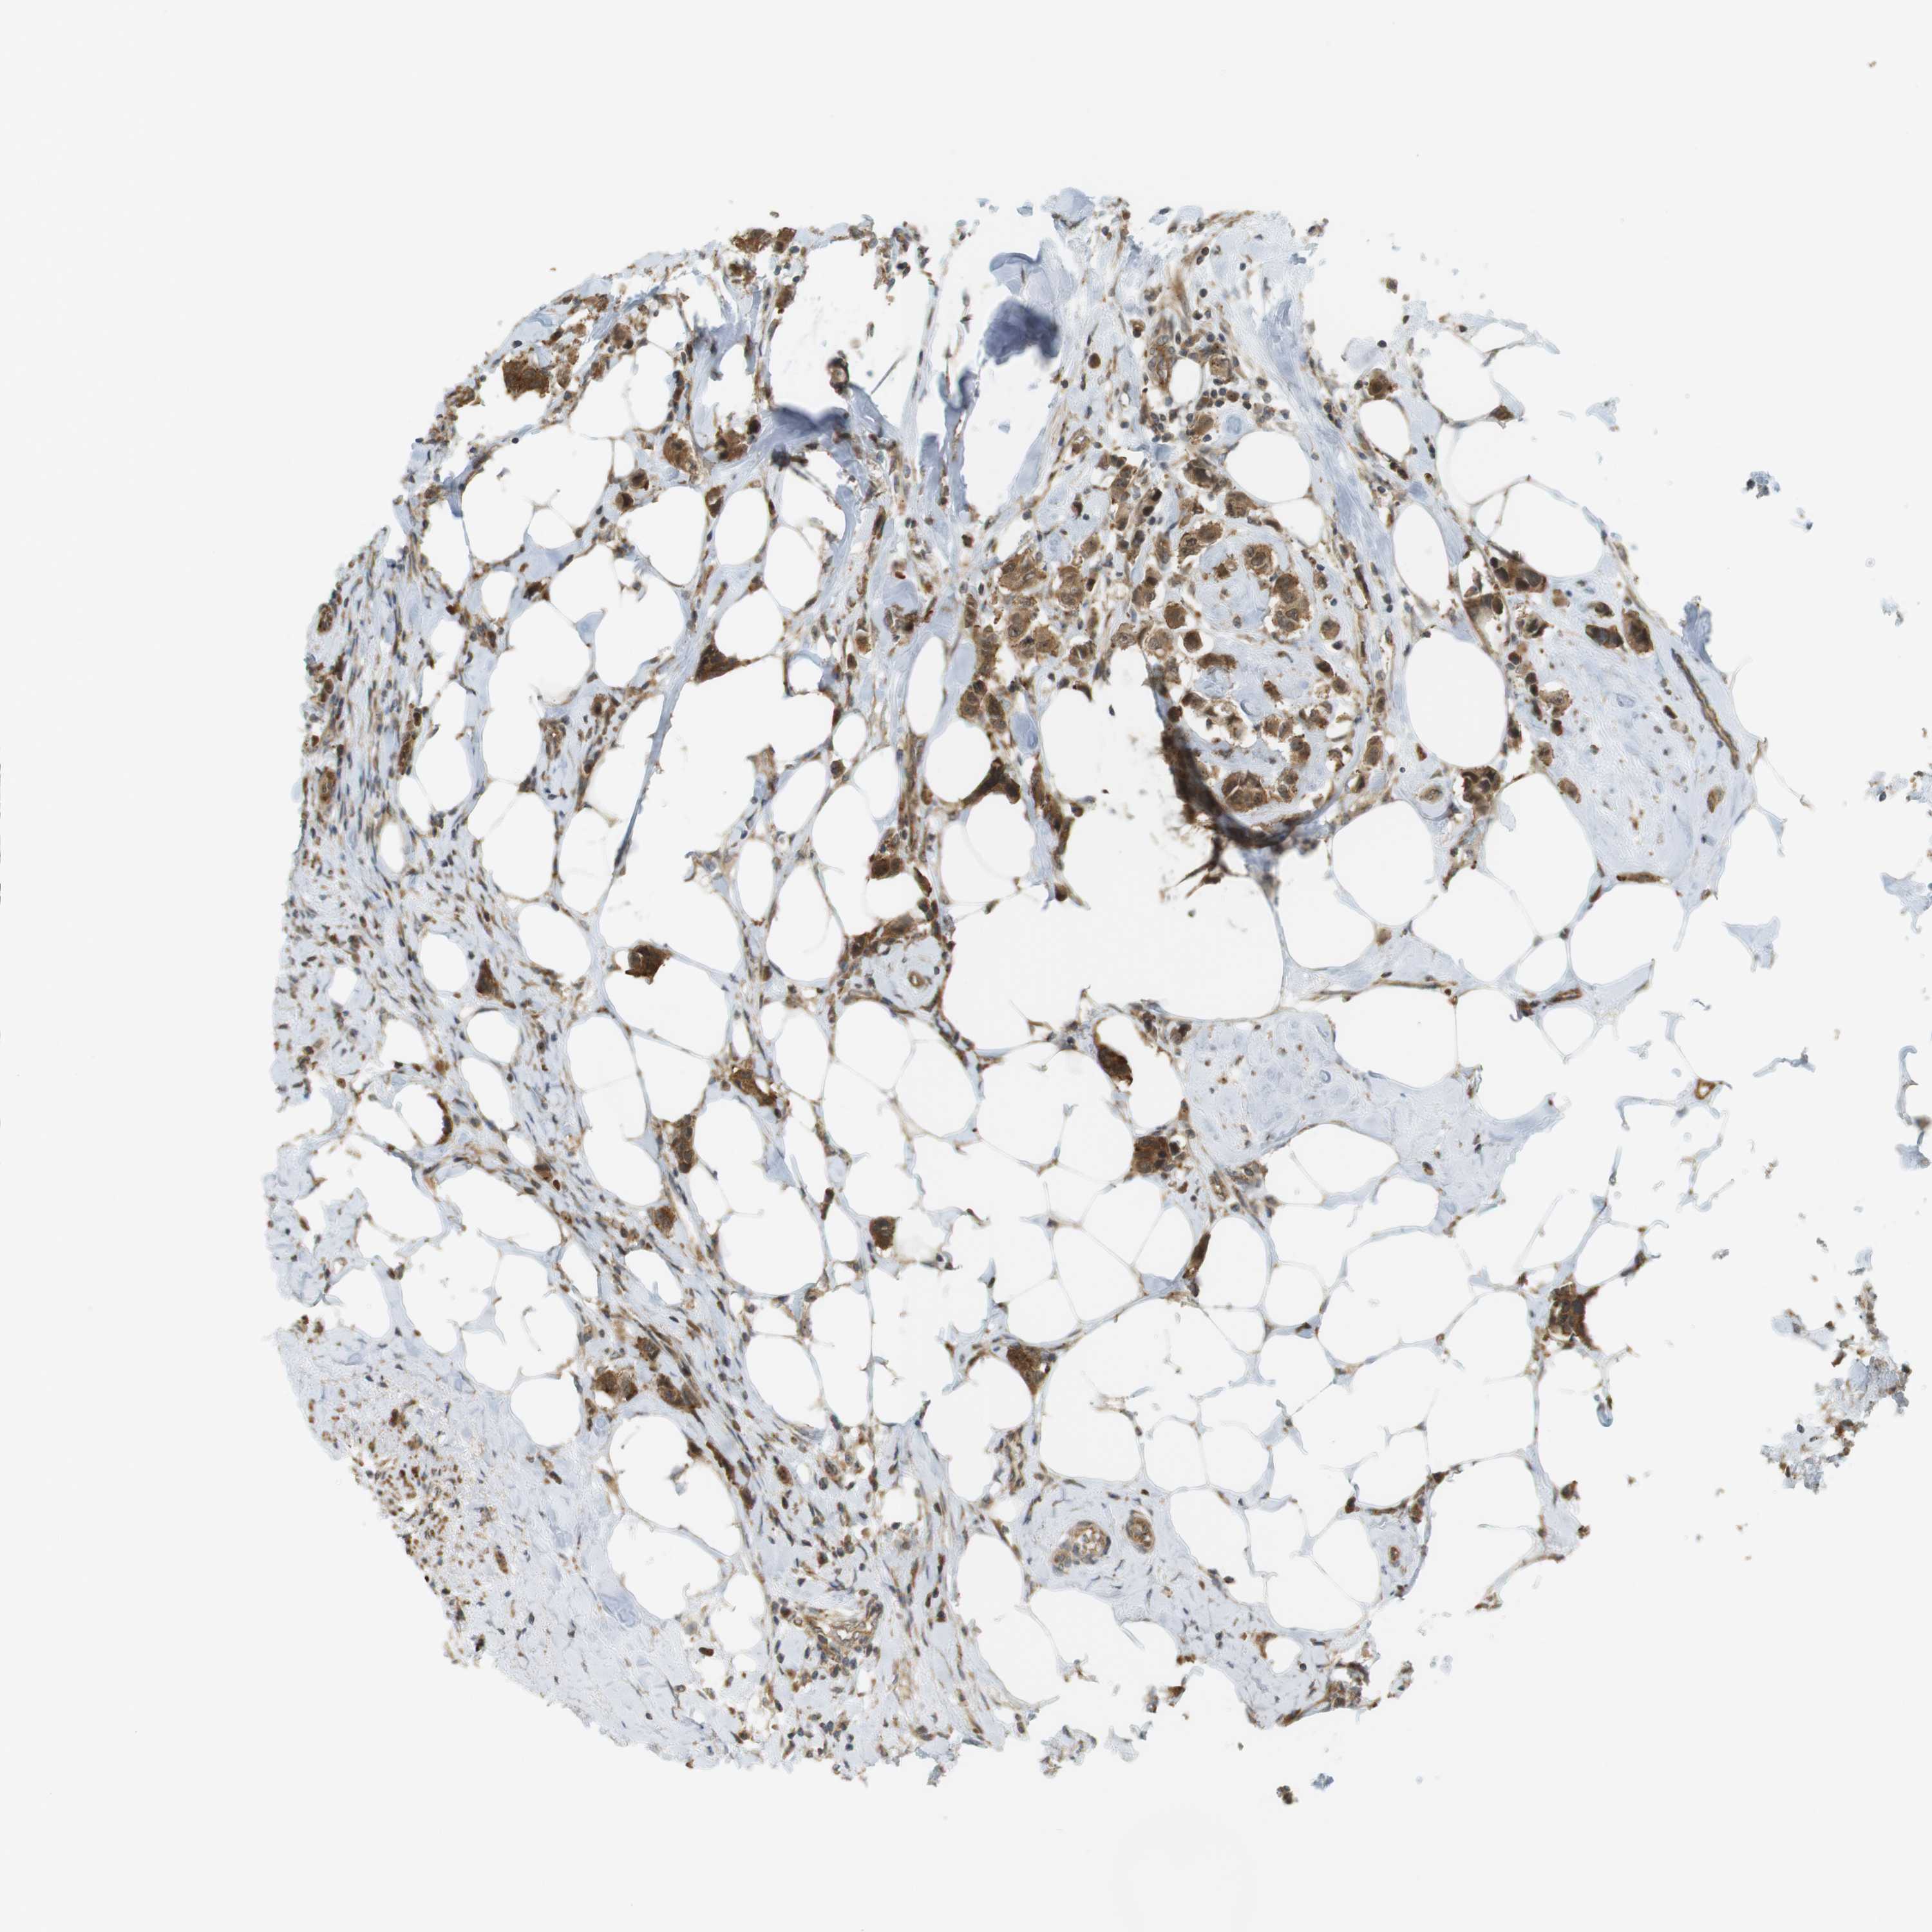

Breast cancer

Human cancer